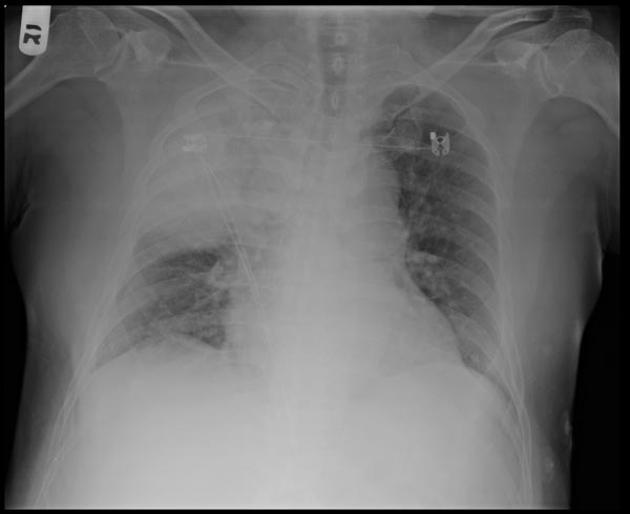

Patient with right lung transplant 3 days ago. Diagnosis? Appearance on CT?

Differential?

Reperfusion pulmonary edema. Noncardiogenic pulmonary edema commonly seen in the first 2-3 days after lung transplant.

On CT, see ground-glass opacities that may progress to consolidation. Start in the perihilar regions. May also see interlobular septal thickening.

If the opacities last beyond 10 days, think of other causes such as rejection or pneumonia.